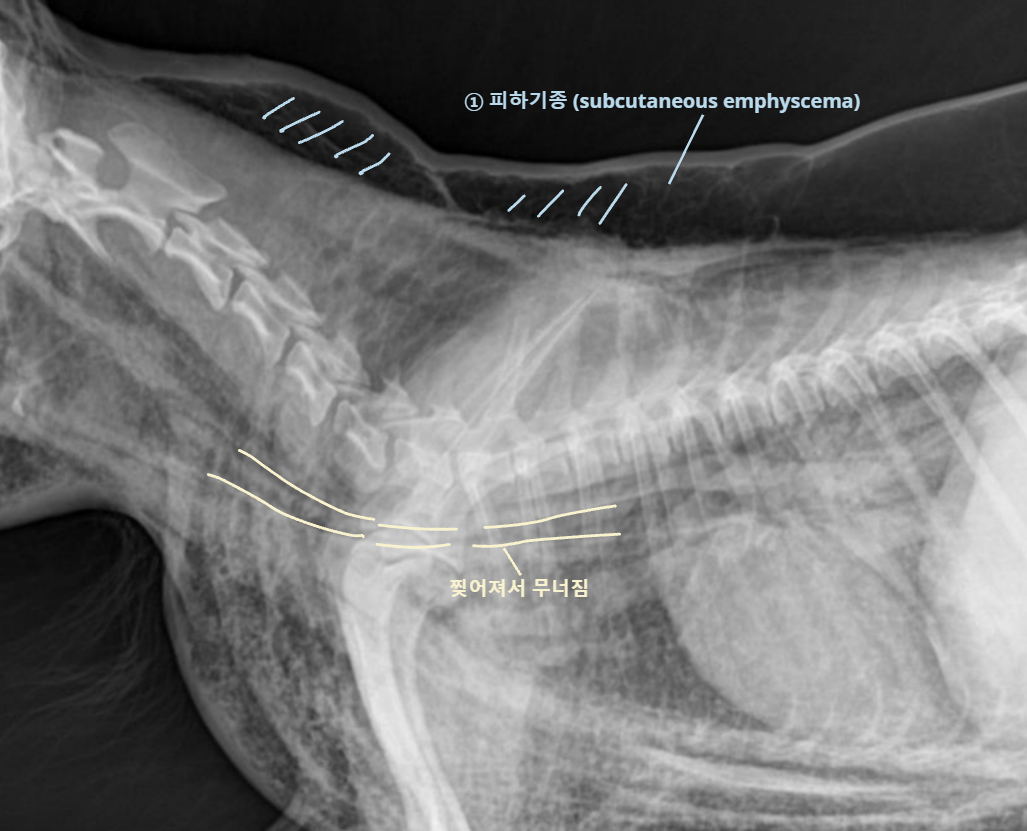

| Tracheal rupture |

![]() |